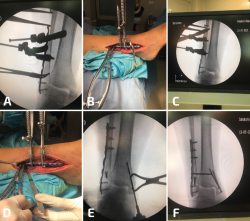

Figura 4. Cuando se realiza la elongación del peroné, este se mueve hacia proximal, evitando la elongación distal. Para evitar esto, se colocan 2 pines proximales a la osteotomía (A). Tras el desbridamiento de la sindesmosis, se elonga el peroné (B) y para mantener la elongación se colocan 2 pines distales a la osteotomía (C) y luego se colocan el injerto y la placa (D).

Una vez más, se desbrida el tejido fibrótico de la cara interna del peroné, pero se deja intacto el ligamento talofibular anterior y el ligamento calcáneo fibular. Para este tipo de osteotomías transversas es importante comprender que, en el proceso de elongación del peroné, al insertar el separador laminar o utilizar el distractor de agujas, se empujará simultáneamente el peroné hacia proximal(10). Por lo tanto, resulta útil insertar 1 o 2 agujas de 1,6 mm en el peroné en la zona proximal a la osteotomía pasando por la tibia para evitar el movimiento del peroné hacia proximal y que solamente se produzca la elongación distal (Figura 4). Una reconstrucción exitosa requiere el posicionamiento anatómico del maléolo externo en la escotadura peronea de la tibia que solo puede detectarse con visualización directa.

La distracción estable es importante durante el procedimiento de elongación del peroné, dado que permite una colocación más sencilla del material de osteosíntesis. Se han descrito varios métodos para poder fijar el astrágalo a la cara interna de la tibia: se pueden utilizar clavos Steinmann desde el peroné distal hasta el astrágalo, o bien se puede insertar una aguja para fijar al astrágalo contra la cara interna de la tibia, cerrando así el espacio de la gotera medial. Otra alternativa sería la utilización de una pinza de reducción de puntas que se coloca en el extremo distal del maléolo externo y el extremo distal del maléolo interno para restablecer el ángulo intermaleolar. Tras una correcta elongación y rotación, se restablece el espacio claro medial, el paralelismo entre las superficies articulares de la tibia y el astrágalo en la mortaja, y una correcta relación entre ambos maléolos (Figura 5).

Figura 5. En este caso, se observa ensanchamiento de la sindesmosis más consolidaciones viciosas del peroné y el maléolo medial (A). Se debe comenzar por la gotera medial para limpiar todo el tejido cicatrizal remanente. La incisión fue más larga de lo habitual, ya que se planificó una osteotomía del maléolo medial. Tras la reducción y la elongación del peroné, se coloca una pinza de reducción en el eje axial entre la tibia y el peroné (C, D). Al continuar con inestabilidad posterior a la colocación de 2 tornillos (E), se decidió realizar una artrodesis de la sindesmosis